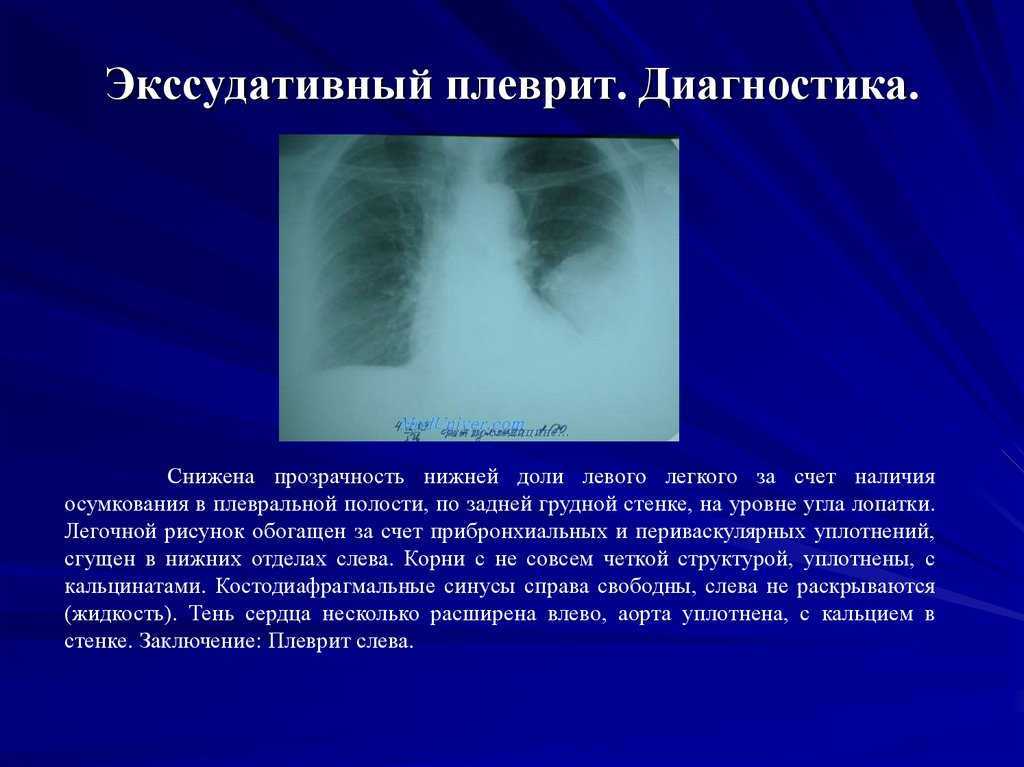

Дифференциальная диагностика заболеваний плевры